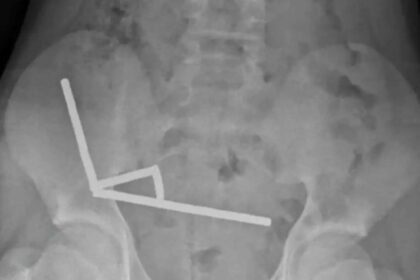

Incident uluitor: Un adolescent de 13 ani a fost supus unei intervenții chirurgicale de urgență după ce a înghițit aproape 200 de magneți.